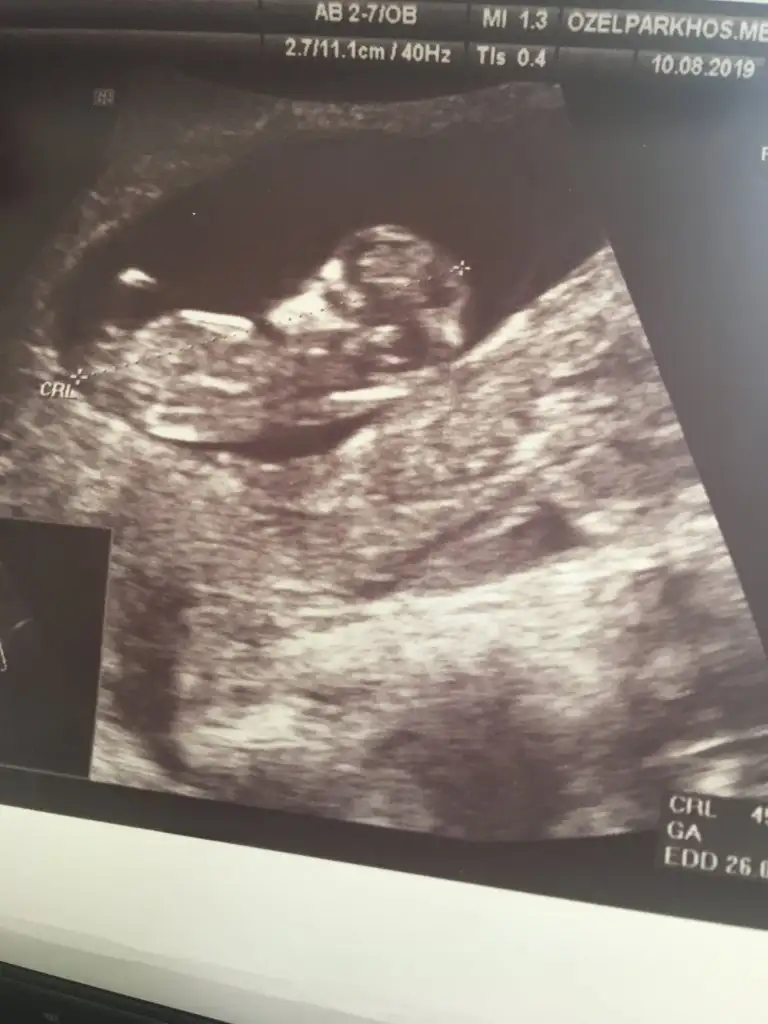

Hadi inşallah banada öyle geldi amaKız bence canım![]()

Bende en başından beri kız hissediyorum 5 gün sonra öğrenmeye gidicez inşallahKız canım bu bebiş

11+4 göre erkek gibi diyorum. Sizce bu nedir 11+4![]()

Hayırlısı neyse o olsun inşallah bazıları kız bazıları erkek diyor bende çok arada kaldım11+4 göre erkek gibi diyorum

Gönlünüzdeki olsun inşallahHayırlısı neyse o olsun inşallah bazıları kız bazıları erkek diyor bende çok arada kaldım5 gün sonra net öğrenicez inşallah